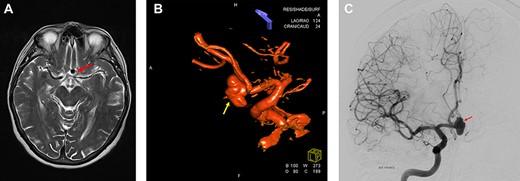

MRI and digitally subtracted angiography showed a large multi-lobulated Acom aneurysm approximately sized 13.0 × 7.5 mm (Fig. 1A–C).

Preoperative neuroimaging. (A) MRI T2-weighted sequence shows an Acom aneurysm without thrombosis. (B, C) Digital subtraction angiography shows a multi-lobulated Acom aneurysm approximately sized 13.0 × 7.5 mm. (B) 3D Digital subtraction.